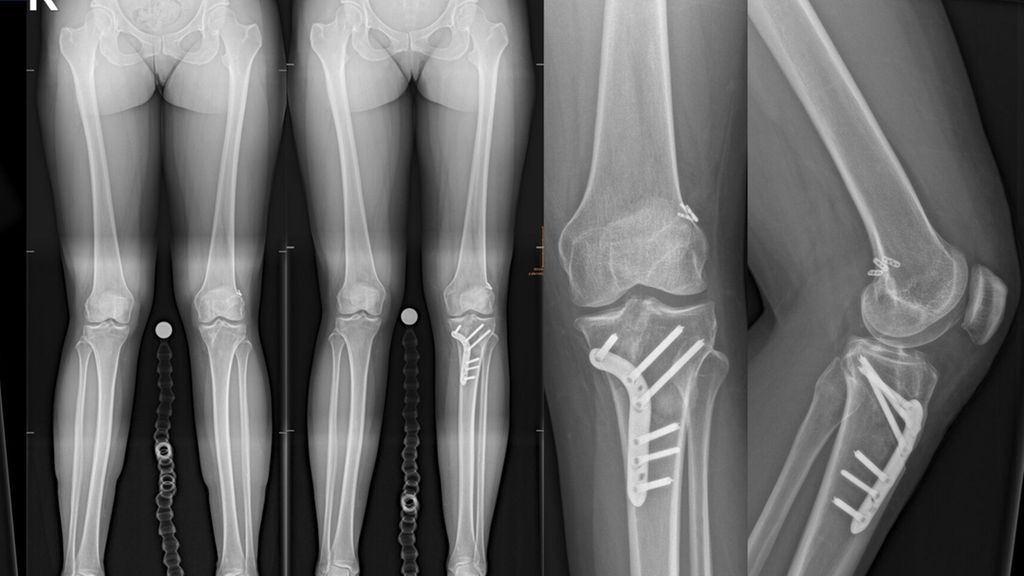

Knöcherne Achsfehlstellungen der unteren Extremität beeinflussen die Biomechanik des Kniegelenks maßgeblich und stellen relevante Risikofaktoren für Rupturen des vorderen Kreuzbandes (VKB) sowie für das Versagen von VKB-Rekonstruktionen dar. Insbesondere im Revisionssetting rücken sagittale und koronare Fehlstellungen zunehmend in den Fokus der differenzierten Therapieplanung.